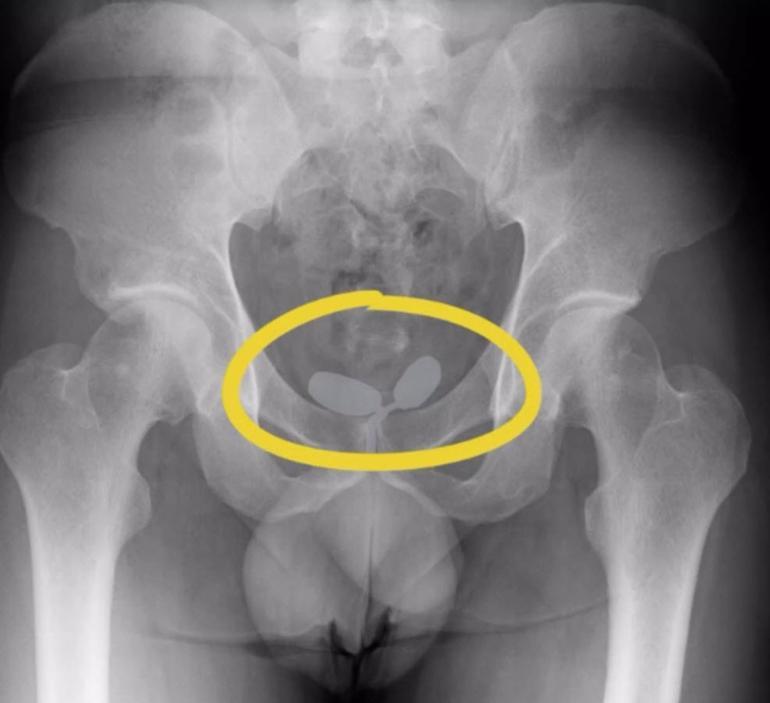

İl Emniyet Müdürlüğü Narkotik Suçlarla Mücadele Şube Müdürlüğü ekipleri, istihbarat çalışması ile yurt dışından İzmir'e uyuşturucu getirileceğini bilgisine ulaştı. İzmir Adnan Menderes Havalimanı'nda, 9 Ekim'de önlem alan ekipler, tespit edilen 2'si Alman uyruklu 5 şüpheliyi durdurdu. Şüphelilerin yapılan iç beden muayenesinde, prezervatifler içinde yutulmuş ve vücut boşluklarına gizlenmiş halde 21,19 gram eroin, 12,70 gram kokain, 7,76 gram metamfetamin ve 7 sentetik hap ele geçirildi. Gözaltına alınan şüpheliler, dün adliyeye sevk edildi. Şüphelilerden Almanya vatandaşı A.D.M. ve F.M. tutuklandı, diğerleri adli kontrol şartıyla serbest bırakıldı.